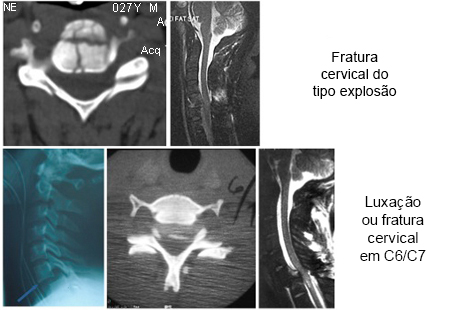

Padrões de fratura comuns com trauma grave da coluna cervical. Linha superior: fratura cervical do tipo explosão no nível de C5. Esquerda: imagem de tomografia computadorizada (TC) axial mostrando uma fratura no corpo vertebral C5; direita: ressonância nuclear magnética (RNM) sagital mediana ponderada em T2, mostrando a retropulsão do corpo vertebral C5 com compressão da medula espinhal, alterações de sinal na medula espinhal ponderadas em T2 e alterações de sinal no complexo ligamentar posterior ponderadas em T2, indicando a ruptura desses ligamentos. Linha inferior: fratura-luxação no nível de C6-C7. Da esquerda para a direita: radiografia lateral, TC axial ao longo do nível C6/C7 da faceta e RNM sagital mediana ponderada em T2 demonstrando compressão da medula espinhal e alteração de sinal na medula espinhal ponderada em T2

Do acervo pessoal de Michael G. Fehlings